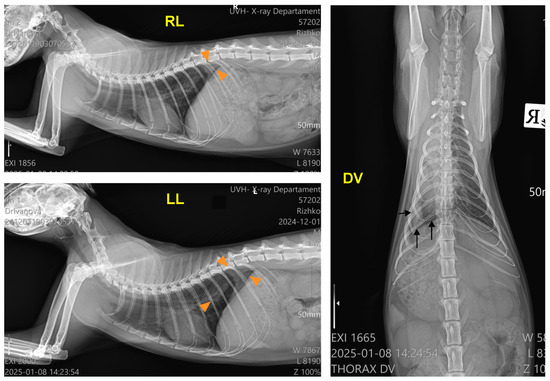

After the physical examination, three chest radiographs were taken in the left lateral, right lateral, and dorsoventral views with stationary radiography equipment (Philips, Bucky Diagnost CS4, Amsterdam, The Netherlands), the iQ-CR ACE digitiser system and iQ-VIEW/PRO version 2.7 software. The exposure data were 50 kVp and 10 mAs. The radiographs showed a bilateral pleural effusion with a clear horizontal boundary. The heart, the mediastinum, and the cranioventral and middle lung lobes on the right lateral view were obscured by the collected fluid. The left lateral view visualised a retraction of the lung lobes away from the dorsal chest wall, radiopaque interlobar fissure lines, rounding of lung margins, and moderate atelectasis. On the dorsoventral view, the trachea was displaced to the right side, and the left lung lobes were obscured by the exudate (Figure 1).

Figure 1. Right lateral (RL), left lateral (LL), and dorsoventral (DV) radiographs of the patient before the thoracentesis, demonstrating accumulated fluid (arrows; RL view), retraction of the lung lobes (black arrowheads, LL and DV views), pleural fissure lines (arrows, LL and DV views), and displacement of the trachea (orange arrowheads, DV view).